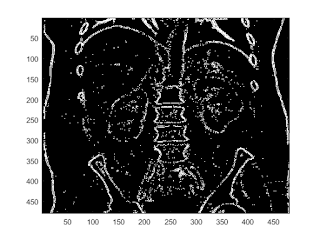

prewitt edge filter

b = fspecial('prewitt'); I2 = conv2(I,b.','same'); imagesc(abs(I2)); colorbar caxis([0,300])

imagesc(abs(I2)>150)